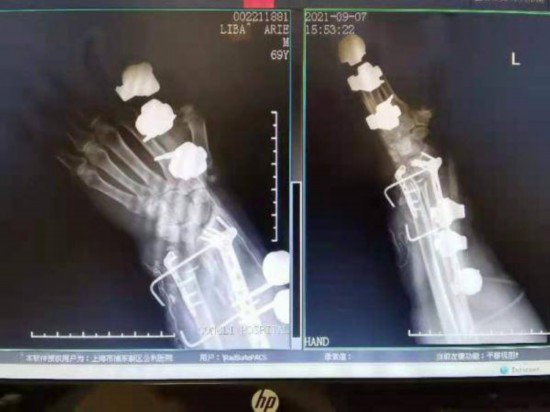

手術開始了。楊鐵毅團隊為老安進行了鋼板內固定結合外固定支架治療,同時行負壓吸引防止術后感染。術后,在鋼板和支架的幫助下,老安的左手在康復治療中慢慢恢復!盎颊咧霸心X梗病史,左側肢體無力,左手肌力弱因此保護性較差,所以跌倒的后果比較嚴重!睏铊F毅也耐心囑咐老安,骨折康復后還應長期進行肌力鍛煉,定期隨訪。